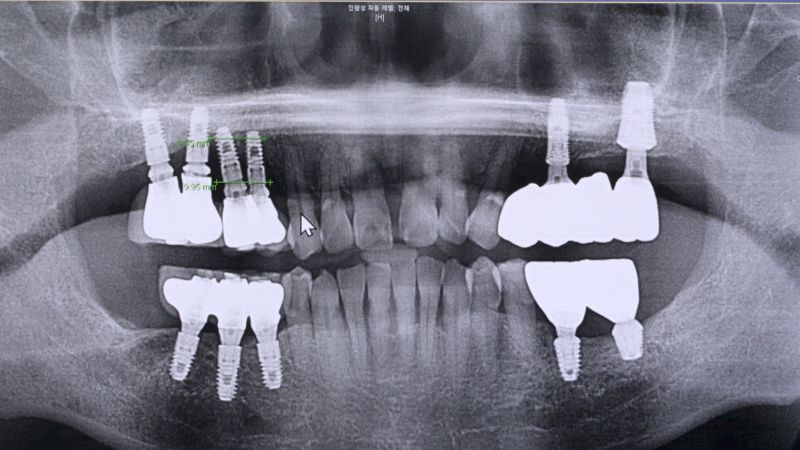

착잡한 얼굴로 병원을 찾은 70대 남성. 남성은 10여 년 전 상악에 심은 임플란트 대부분을 제거하고 남은 한 개로 임플란트 틀니를 사용하고 있었다. 하지만 그마저도 염증이 발생해 더 이상 사용이 어려워졌다. 남성은 임플란트 재식립을 원하지만 염증으로 치조골이 심각하게 녹아 재식립이 어려운 상황. 결국 남은 선택지는 틀니밖에 없었다.

임플란트 식립의 가장 중요한 조건은 충분한 양의 치조골이다. 그런데 임플란트 주위염은 치주염보다 훨씬 더 진행 속도가 빠르며 치주조직과 뼈를 파괴적으로 손상시키기 때문에 조기에 치료하지 않으면 임플란트가 헐거워져 빠지게 되고, 그 이후 재식립도 할 수 없다.

한 달 전부터 위쪽 어금니 임플란트에 통증을 느꼈다는 여성. 검사 결과 식립한 임플란트 고정체가 부러진 채 뼈에 박혀있는 상태였다. 실제로 통계에 따르면 임플란트 부작용 중에 나사 풀림과 파절이 약 49%로 1위를 차지한다.

임플란트의 나사가 풀리면 다시 조여주기만 하면 되지만 여성의 경우 나사가 잇몸에 고정된 채 부러져 제거하고 재식립 해야 하는 상황이다. 보철과 윤준호 교수는 임플란트를 제거하는 것은 임플란트를 식립하는 것보다 훨씬 어렵다고 말한다.

임플란트는 식립한 순간부터 주변 뼈와 유착이 이루어진다. 치주인대가 없이 나사못과 뼈가 바로 붙어 있기 때문에 제거 시 뼈 손상이 불가피하다. 따라서 신중하게 제거하지 않으면 상악동이 뚫리거나 하악의 경우 수많은 신경다발이 지나가기 때문에 신경 손상으로 마비, 통증 등을 유발할 수 있어 매우 신중해야 한다. 그렇다면 임플란트 제거술은 어떻게 진행되는 것일까? 임플란트 제거술과 나사 풀림과 파절이 발생하는 원인 및 임플란트를 망가트리는 습관 등을 자세히 알아본다.